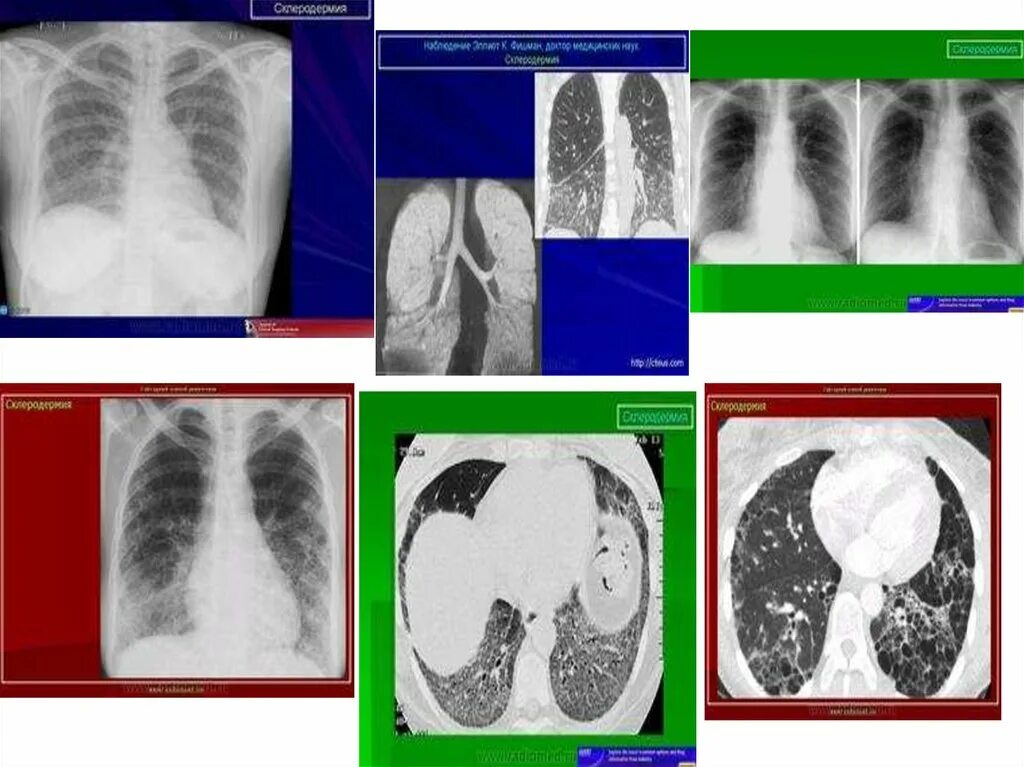

Диффузную системную склеродермию